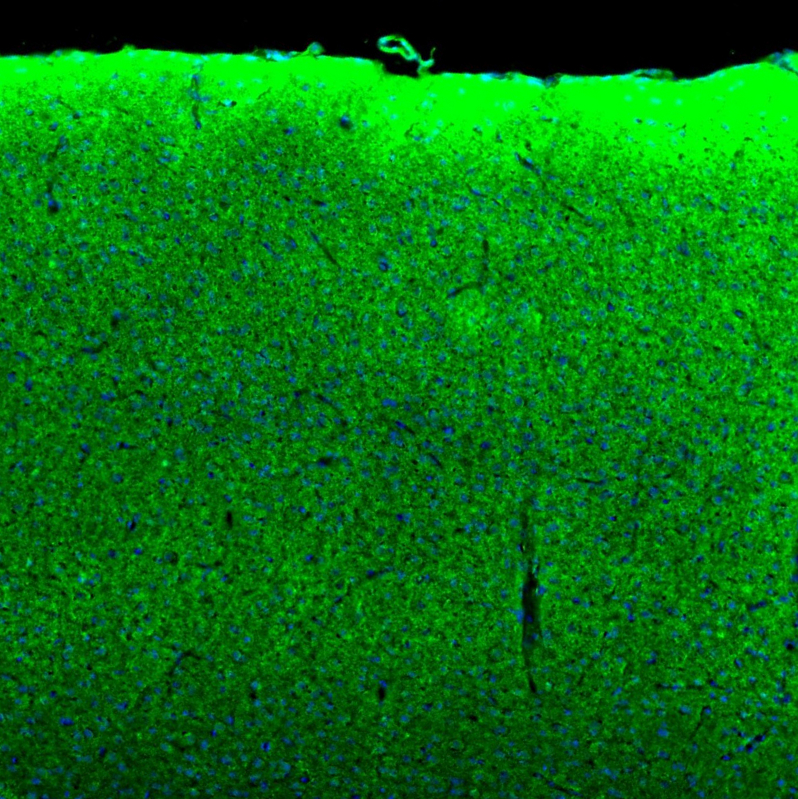

Immunohistochemical staining of human duodenum shows strong granular cytoplasmic positivity in glandular cells.